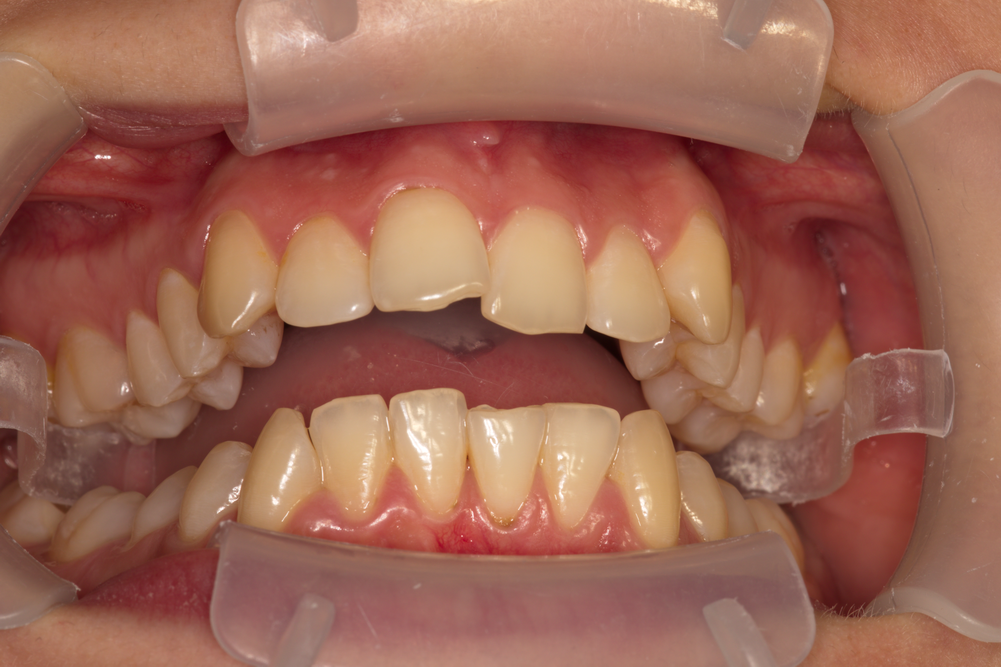

Снимка на пациент с минимални деформации, но с необходимост от ортодонтска намеса - жена на възраст 22 години